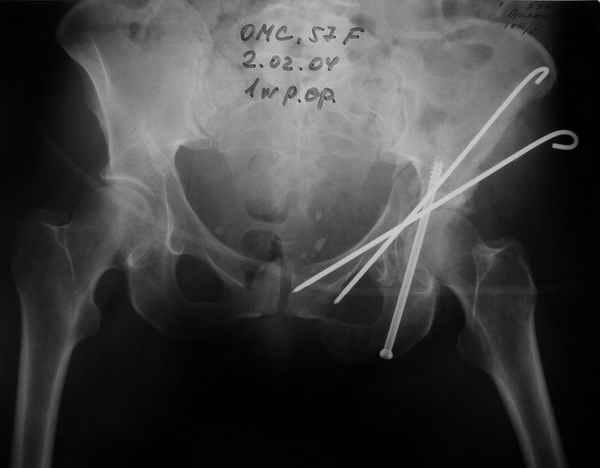

27.01.04

02.02.04

10.02.04

Anatoly F Lazarev 03 Сентябрь 2004, 22:18

Женя! Класный перелом. Отлично репонируется изнутри таза, но лучше фиксированть сзади. Классический перелом для двустороннего доступа.

Высылаю пример еще одного случая, остеосинтез пластиной из подвздошного доступа.